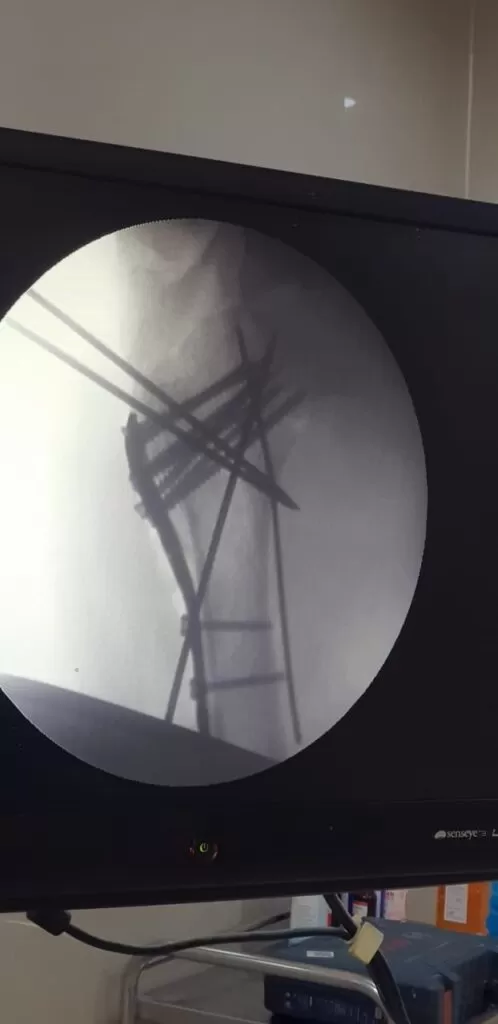

Mr. Akeel

Name: Mr. Akeel

Date of Operation: 10 Mar 2024

Age: 46 Years

Complex Trauma